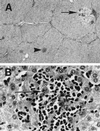

A novel virus, designated swine hepatitis E virus (swine HEV), was identified in pigs. Swine HEV crossreacts with antibody to the human HEV capsid antigen. Swine HEV is a ubiquitous agent and the majority of swine >/=3 months of age in herds from the midwestern United States were seropositive. Young pigs naturally infected by swine HEV were clinically normal but had microscopic evidence of hepatitis, and developed viremia prior to seroconversion. The entire ORFs 2 and 3 were amplified by reverse transcription-PCR from sera of naturally infected pigs. The putative capsid gene (ORF2) of swine HEV shared about 79-80% sequence identity at the nucleotide level and 90-92% identity at the amino acid level with human HEV strains. The small ORF3 of swine HEV had 83-85% nucleotide sequence identity and 77-82% amino acid identity with human HEV strains. Phylogenetic analyses showed that swine HEV is closely related to, but distinct from, human HEV strains. The discovery of swine HEV not only has implications for HEV vaccine development, diagnosis, and biology, but also raises a potential public health concern for zoonosis or xenozoonosis following xenotransplantation with pig organs.